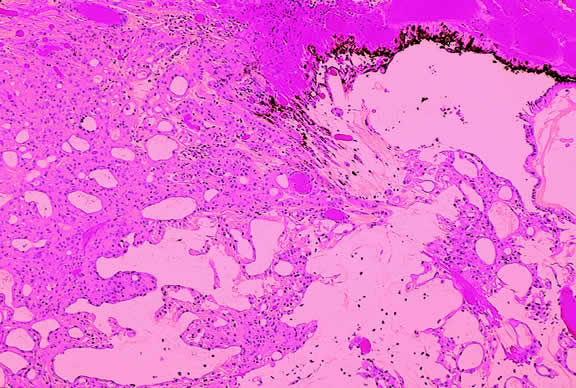

Most of the solid tumors that metastasize to the uvea are carcinomas; sarcomas rarely metastasize to the eye. Although any part of the eye may be involved by metastatic tumor, the uveal tract, especially the posterior part of the choroid, is affected most often (Fig. 48). A retrospective review of 520 eyes with uveal metastases in 420 patients evaluated by the Oncology Service at the Wills Eye Hospital during a 20-year period showed that 88% of 950 metastatic foci involved the choroid.185 The iris was involved in 9% and the ciliary body in 2%. Most of the choroidal metastases involved the macula (12%) or the region between the macula and the equator (80%). The posterior choroid is affected most often because its blood supply is greater. Metastases to the retina, vitreous, and optic disc are relatively uncommon.186–190

Fig. 48. Metastatic breast carcinoma. The posterior pole contains multiple nodules of amelanotic tumor. The patient was known to have metastatic mammary carcinoma. (Photo courtesy of Dr. Carol L. Shields, Wills Eye Hospital)

Choroidal metastases typically appear as yellow or creamy yellow, nummular, sessile dome- or plateau-shaped masses (see Fig. 48). A secondary serous retinal detachment usually is present. The metastases may be solitary or multiple and occasionally may involve both eyes. In a study by Shields and associates,185 29% of the eyes contained 2 or more metastases, and 17% contained three or more foci of metastatic tumor. Visual loss usually is caused by the exudative retinal detachment, which often has shifting subretinal fluid. Metastases usually are creamy yellow in color but can appear partially pigmented if necrosis has produced dispersion of uveal pigment. Metastases from skin melanomas are often grayish or brown. Metastases from carcinoid tumors, thyroid carcinoma, or renal cell carcinomas may be orange in color.

Breast and lung carcinomas are the primary tumors that metastasize to the uvea most often and are responsible for more than two thirds of cases.185,194 Nearly half (47%) of the 420 patients reported by Shields and associates had breast carcinoma, and about one fifth (21%) had lung cancer. Other primary tumors included gastrointestinal tract (4%), kidney (2%), skin (2%), prostate (2%), and other cancers (4%).185 The primary tumor may be occult when the patient presents to the ophthalmologist. In Shields' series, one third of the patients had no history of a primary cancer at the time of ocular diagnosis. Subsequent evaluation showed that the occult primary tumor was lung carcinoma in 35% and breast carcinoma in 7%. However, no primary tumor was discovered in 51%. Women with metastases from breast carcinoma usually have a prior history of mastectomy; only 5% in the Shields' series presented with an occult mammary tumor. In contrast, metastasis often was the presenting manifestation of an occult lung cancer; only 45% of the cases with metastatic lung cancer were know to have cancer when the ocular diagnosis was made. Metastatic lung cancer is more common in men.

The prognosis of patients with uveal metastasis generally is quite poor; the mean survival has been reported to be approximately 9 to 10 months.195,196 Treatment is recommended if the metastasis appears active and is threatening vision or the globe.185 Radiation therapy is recommended if the metastasis is symptomatic or continues to grow despite systemic chemotherapy. Plaque brachytherapy is advantageous compared with external beam radiotherapy because it can be delivered over a relatively short period of the patient's limited remaining life span.

The diagnosis of intraocular metastasis usually is made by slit lamp biomicroscopy and ophthalmoscopy in the patient who has been carefully questioned about a past medical history of cancer. Ancillary techniques such as intravenous fluorescein angiography and ultrasonography often can assist in making the diagnosis. Metastases generally begin to show hyperfluorescence in the late venous phase fluorescein angiography, somewhat later than most melanomas or hemangiomas.48,54 Metastases have many acoustical interfaces because they are composed of nests, cords, and island of tumor cells surrounded by stroma. Hence, they show high internal reflectivity on A scan ultrasonography and appear acoustically solid in B scan, characteristics they share with hemangiomas (Fig. 49). In cases in which the results from other studies are equivocal, cytopathologic examination of material obtained by fine-needle aspiration biopsy may establish the diagnosis.82,83

Macroscopically, the appearance of eyes with uveal metastases is somewhat variable. In most instances the uveal tract is diffusely thickened by an infiltrate of white, pink, or yellow tissue (Fig. 50). Metastases occasionally have a multinodular growth pattern, and a few larger lesions are oval in configuration (Fig. 51). Bruch's membrane almost always remains intact, however. Although there are exceedingly rare exceptions to the rule, one generally can conclude that a mushroom-shaped tumor of the choroid is a malignant melanoma.

Microscopically, the uveal stroma is infiltrated by nest, cords, islands, and sheets of tumor cells whose general appearance and arrangement is dependent on the identity of the primary neoplasm. Most of the breast and lung tumors that metastasize to the eye are mucous-secreting adenocarcinomas. In such cases special stains such as Alcian blue, PAS, or mucicarmine are used to demonstrate the presence of intracytoplasmic mucin (Fig. 52). In most instances the pathologist can readily distinguish between a primary uveal melanoma and metastatic carcinoma in routine sections. Immunohistochemistry may be helpful in exceptional cases. Carcinomas are distinguished by positive immunoreactivity for epithelial markers such as cytokeratins and epithelial membrane antigen. Most melanomas stain with S-100 protein and vimentin and a variety of other markers including so-called melanoma specific antigen HMB-45, melan A, and microphthalmia factor. Occasionally, immunohistochemistry can confirm or provide clues to the identity of the primary tumor by demonstrating the presence of tumor specific antigens such as prostate specific antigen (PSA) in prostatic carcinoma or thyroglobulin in thyroid. Distinguishing between a primary uveal melanoma and choroidal metastasis from skin melanoma or another primary nonocular pigmented neoplasm may be challenging.197,198